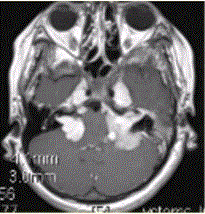

女性,15岁。MR表现如下图,可能的诊断是A.神经纤维瘤病I型B.神经纤维瘤病II型C.结节性硬化D.双侧听神经瘤E.颜面血管瘤综合征

问题 女性,15岁。MR表现如下图,可能的诊断是

选项 A.神经纤维瘤病I型 B.神经纤维瘤病II型 C.结节性硬化 D.双侧听神经瘤 E.颜面血管瘤综合征

答案 B